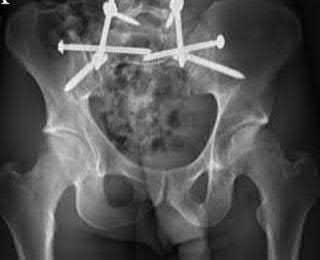

Question 3:

A 55-year-old male undergoes excision of a large cartilaginous tumor of the proximal femur. Molecular analysis of the tumor reveals a mutation in the isocitrate dehydrogenase 1 (IDH1) gene. This mutation is a hallmark of and most frequently associated with which of the following conditions?

Correct Answer: Ollier disease

Explanation:

Mutations in the IDH1 and IDH2 genes are heavily implicated in the pathogenesis of cartilaginous tumors. Somatic mosaic mutations in these genes are found in over 80% of patients with Ollier disease and Maffucci syndrome, both of which are forms of enchondromatosis. Multiple Hereditary Exostoses is associated with EXT1/EXT2 mutations. McCune-Albright is associated with GNAS mutations. NF1 is associated with the neurofibromin gene.